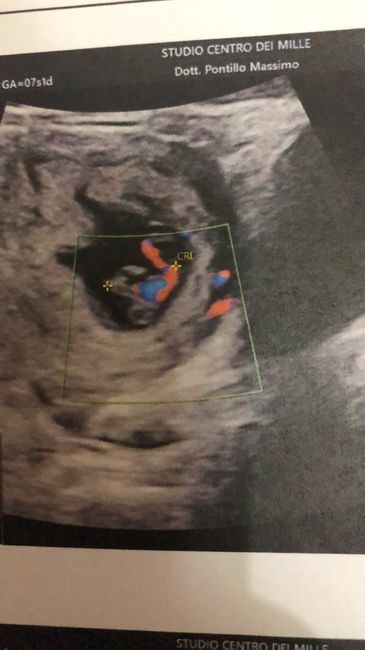

Buongiorno!! Chi è brava a spiegarmi il metodo Ramzi e sa azzeccarci? 😊